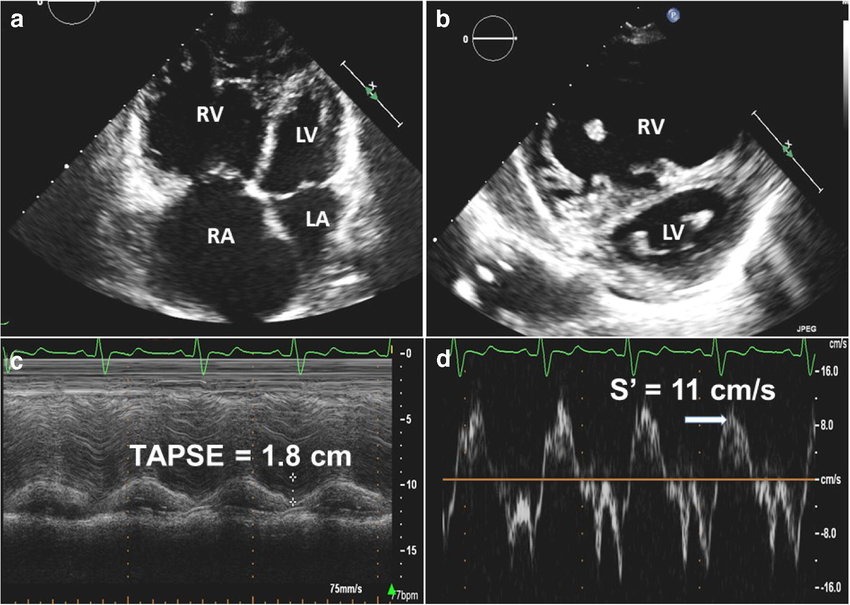

But CAD doesn't only affect the left ventricle.

Right ventricular infarction can occur, especially with right coronary artery occlusion.

Echo findings may include:

🔵 RV wall motion abnormalities

🔵 Reduced TAPSE

🔵 RV dilation Calculation of fractional area change (FAC) from tracings of end-diastolic area (EDA) and end-systolic area (ESA) of the right ventricle.

Image